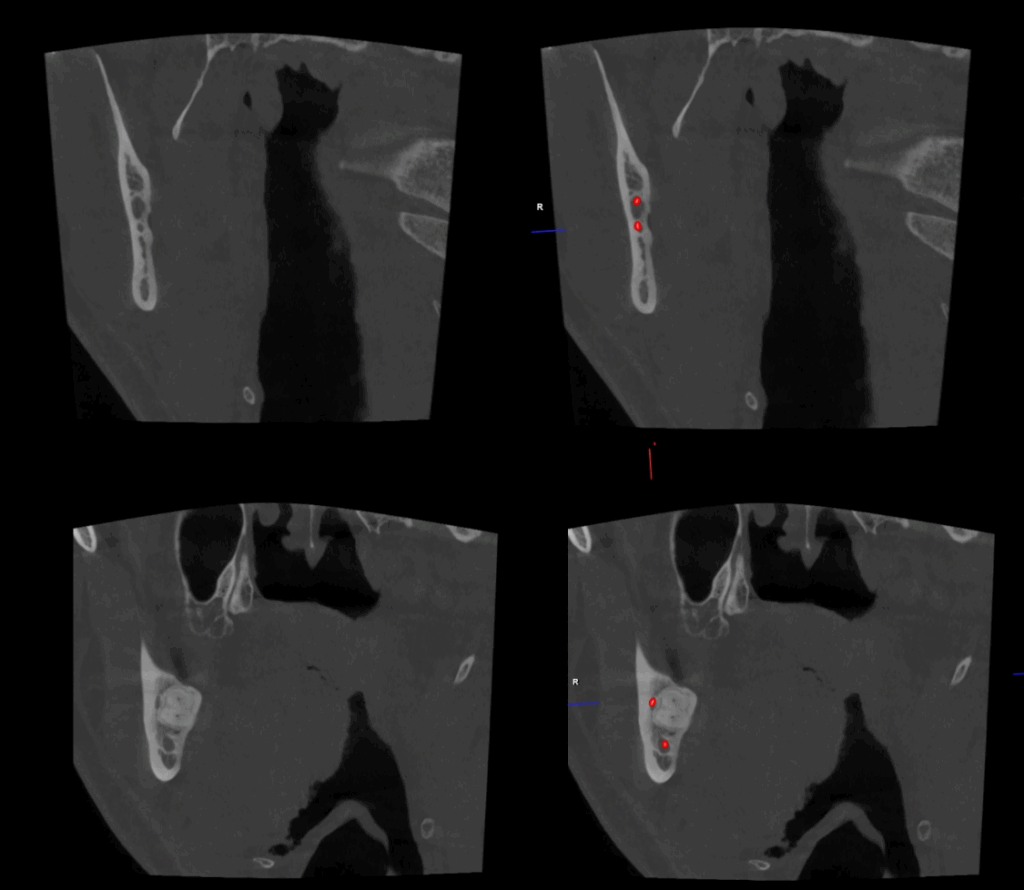

CORTES CORONALES

caso 344 - CORTES CORONALES IDM